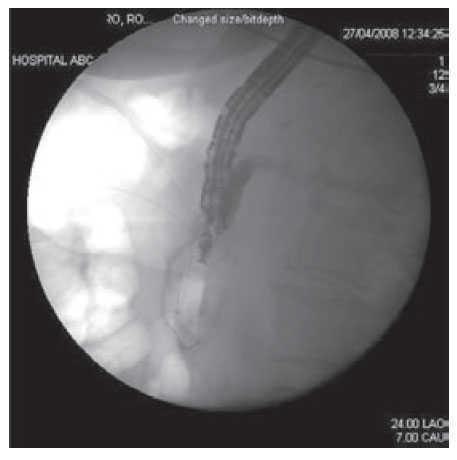

Once the wire was into the duodenal lumen several loops were formed (Figure 3) in order to avoid loosing access at the time endoscope exchange during the rendezvous procedure that was performed as previously described. (Figure 4 A-C). Using a duodenoscope (TJF-160F, Olympus) we observed that the bile duct drained from an independent and different orifice than the pancreatic duct within the ampulla. Access and drainage of the bile duct was performed sliding the duodenoscope over the guide wire; during the procedure, self-limited blood oozing occurred after biliary sphincterotomy. The patient underwent surgery next day and was discharged in good conditions.

Figure 3. Fluroscopic image showing a 0.018 inch guide wire inserted through the needle and advanced in an antegrade fashion, into the duodenum across the papillary orifice.